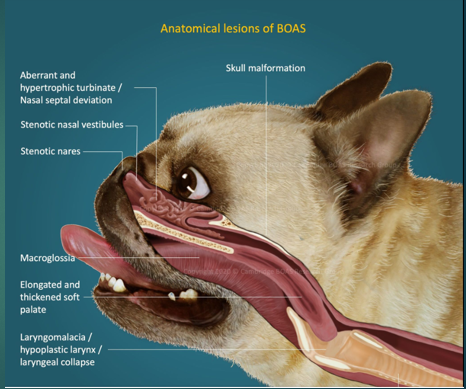

Brachycephalic obstructive airway syndrome in Dogs

Bulldog

Pug

Pekingese

French Bulldog

Boxer

Stenotic nares

Narrowing of the nasal passages, this increases resistance, making breathing in and out more difficult for the paitent

Oversized tongue

Tongue is too big for their moth, can push on soft plate

Elongated soft palate

Effects the epiglottis so can aspirate more easily

Hyperplastic larynx

Overgrowth of soft tissue in the larynx, leading to obstruction

Hypoplastic trachea

Trachea is narrower

Brachycephalic obstructive airway syndrome

The problems we see in these breeds are the consequences of trying to move air with all this increased resistance. To breathe they need to move O2 through the resp tract to the lungs, these issues with the soft tissues that we’ve highlighted cause resistance to air flow, this then increases Resp effort and rate to get more air in, this increases the negative pressure which makes the issue worse – negative pressure caused by them trying to overcome the resistance means that we get more resistance, more swelling of soft tissues and thus more negative pressure. We will often see abdominal effort with BOAS breathing.